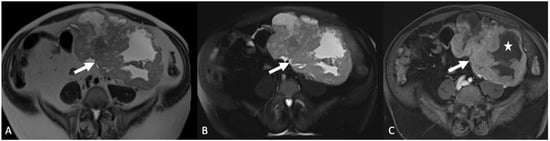

5.3. Peritoneal Disease

5.3.1. Disseminated Peritoneal Leiomyomatosis

5.3.2. Peritoneal Carcinomatosis

5.3.3. Peritoneal Tuberculosis

5.4. Gastrointestinal Lesions